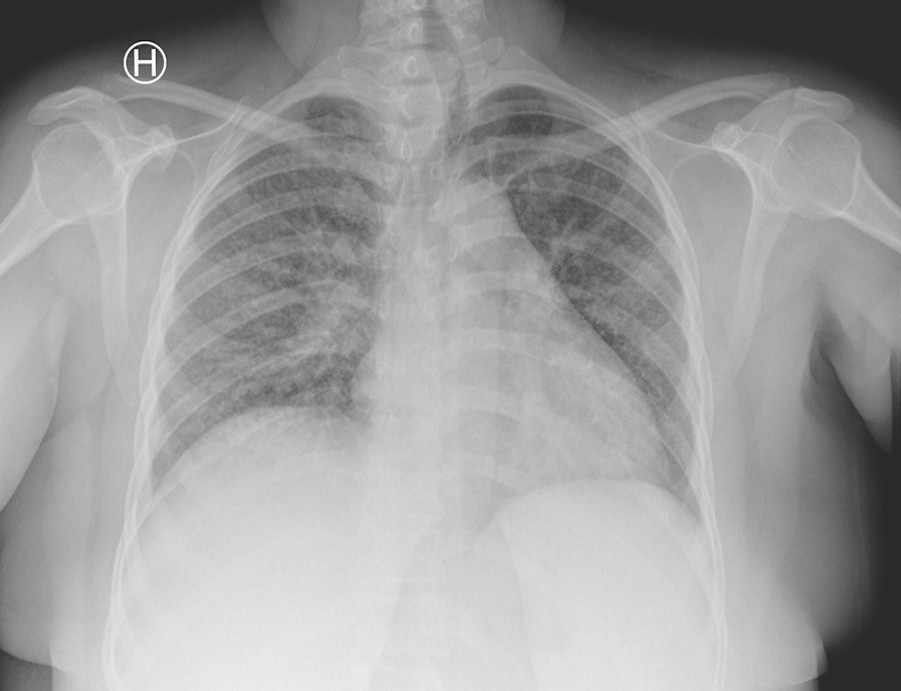

I to uker hadde hun så vekslende feber, svimmelhet og hodepine, etter hvert daglig oppkast, vedvarende tørrhoste og tung pust. Hun ble på nytt henvist til medisinsk avdeling ved lokalsykehuset. Ved innkomst (dag 1) var hun febril med temperatur 38,0 °C, blodtrykk 144/77 mm Hg, puls 101/min, respirasjonsfrekvens 16/min og O2-metning 98 %. CRP-nivået hadde steget til 130 mg/l. Røntgen thorax ved innleggelsen viste diffuse lungefortetninger bilateralt, oppfattet som mulig atypisk pneumoni (fig 1).